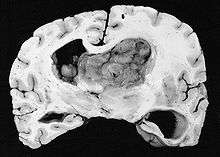

Subependymal giant cell astrocytoma (SEGA, SGCA, or SGCT) is a low-grade astrocytic brain tumor (astrocytoma) that arises within the ventricles of the brain.[1] It is most commonly associated with tuberous sclerosis complex (TSC). Although it is a low-grade tumor, its location can potentially obstruct the ventricles and lead to hydrocephalus.

Diagnosis is made by imaging with a contrast-enhanced MRI or CT scan of the brain.